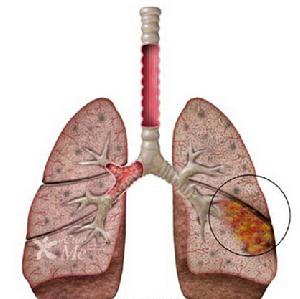

3、X線檢查多表現為單側病變,約占80%以上,大多數在下葉,有時僅為肺門陰影增重,多數呈不整齊雲霧狀肺浸潤,從肺門向外延至肺野,尤以兩肺下葉為常見,少數為大葉性實變影。可見肺不張。往往一處消散而他處有新的浸潤發生。有時呈雙側瀰漫網狀或結節樣浸潤陰影或間質性肺炎表現,而不伴有肺段或肺葉實變。體徵輕微而胸片陰影顯著,是本病病特徵之一。

X線檢查:肺部病變表現多樣化,早期間質性肺炎,肺部顯示紋理增加及網織狀陰影,後發展為斑點片狀或均勻的模糊陰影,近肺門較深,下葉較多。約半數為單葉或單肺段分布,有時浸潤廣泛、有實變。兒童可見肺門淋巴結腫大。少數病例有少量胸腔積液。肺炎常在2~3周內消散,偶有延長至4~6周者。